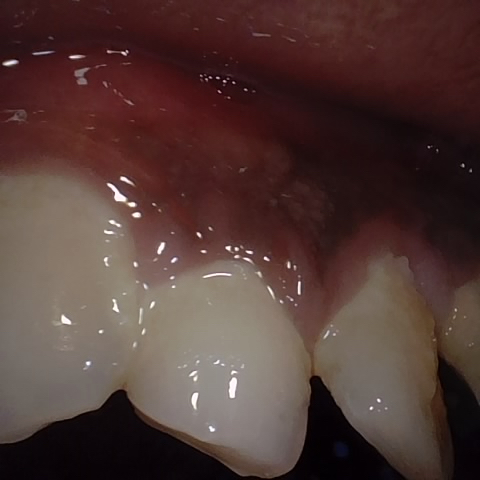

NHD38254

Annotated as "Good"